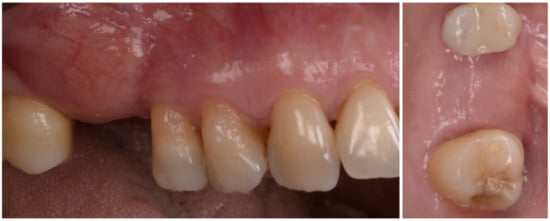

The case has been followed for over three years and the stability of the soft and hard tissue are proof of the GTR effect of GBR. In this case, all parameters were restored in a still very young patient (Figure 12). The important aspect of the GTR effect is that teeth otherwise compromised at a young age are back in function with the support of both soft and hard tissue and all of this with only two surgical procedures. The presence of interdental-implant papilla is important to prevent food impaction and make the maintenance similar to that of the natural dentition. PPD at the time of recall were 2 mm to the distal of 15 and 2 mm to the mesial of 17; compared to the baseline, the gain of attachment was 4 mm for 15 and 5 mm for 17.

Figure 12.

Baseline and clinical and radiographic result 36 months after loading.